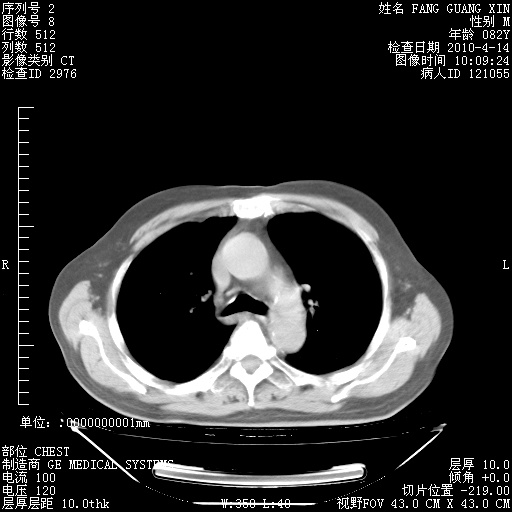

4月14日肺部CT